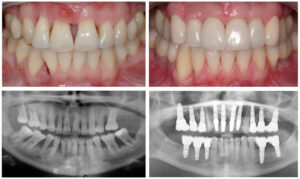

Periodontal-disease-dental-implants

Bone loss doesn’t happen overnight. It’s usually the result of long-term tooth loss, gum disease, ill-fitting dentures, or failed dental work. When bone volume is reduced, traditional implants often require grafting to rebuild the foundation.

This is where All-on-4 gets attention. By angling the rear implants into denser bone areas, it can sometimes bypass grafting entirely.